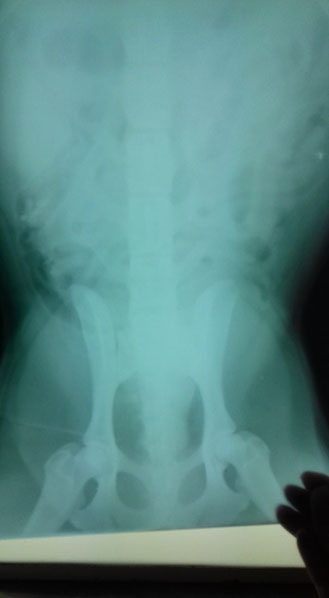

Miglena Dzhurova fand Anfang März 2018 einen verletzten Hund und brachte ihn sofort in die Klinik. Er war von einem Auto angefahren worden. Die Röntgenaufnahmen zeigten leider, dass seine Wirbelsäule gebrochen war - genau an derselben Stelle wie bei Dea aus unserem SOS-Tierschutzprojekt 48.

Dea wurde vor 15 Monaten aus einem Garten gerettet, wo sie mehrere Wochen ohne tierärztliche Versorgung ausgeharrt hatte. Auch bei Dea ergaben damals die Tests, dass sie kein Gefühl mehr in den

Hinterbeinen hatte, auch nicht in tieferen Regionen. Wie Dea kann der Rüde seine Körperfunktionen nicht mehr kontrollieren und wird Windeln tragen müssen… auch er ist jung, ungefähr ein Jahr alt

und hat sein Leben eigentlich noch vor sich.

Und auch bei ihm wird eine Operation keine Besserung erzielen.

Gott sei Dank ist der Bruch seiner Wirbelsäule nicht wie bei Dea verschoben, so dass Hoffnung besteht, dass er seine Hinterläufe wird wieder ein wenig einsetzen können. Dies gelang bereits bei